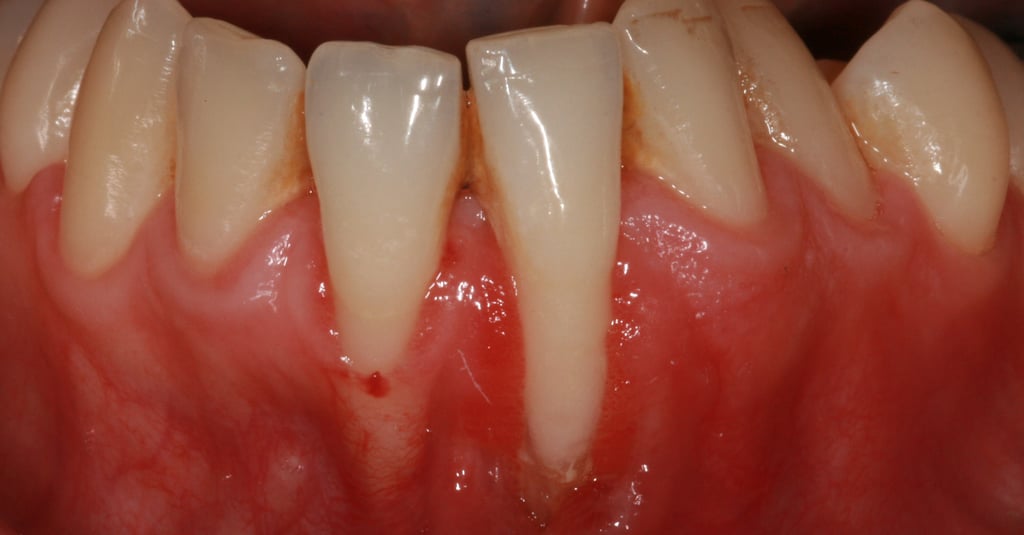

Le recessioni gengivali sono una condizione comune in cui il tessuto gengivale si ritira, esponendo una parte del dente o della radice. Questo problema non è solo estetico, ma può anche compromettere la salute orale.

Denti che sembrano più lunghi